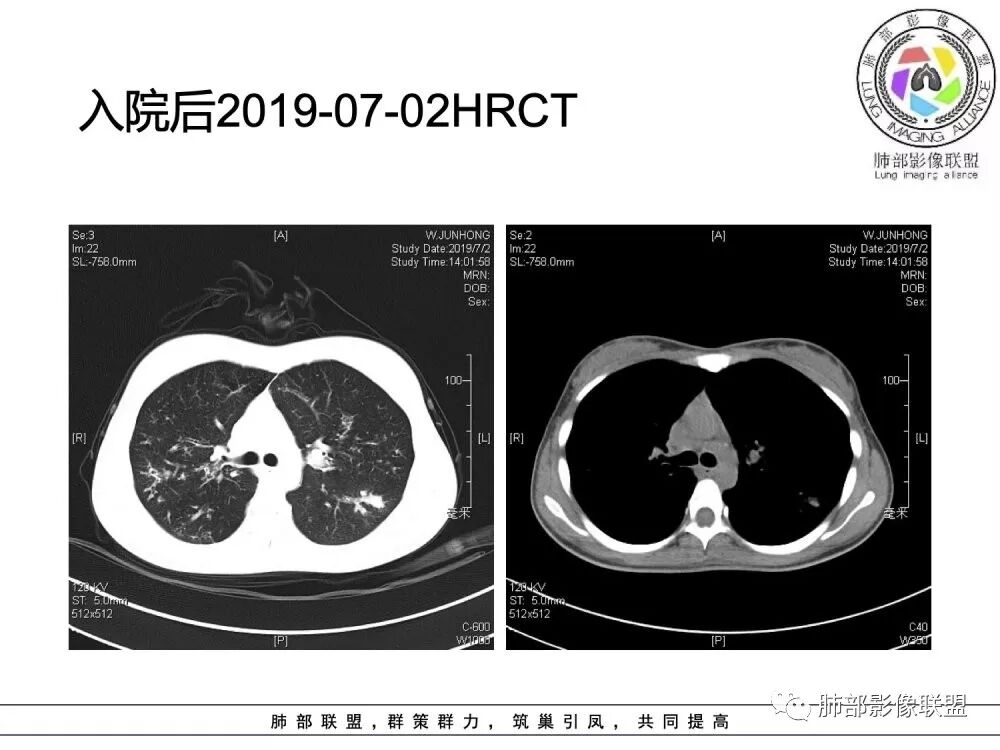

胸部CT检查:

(1)支气管壁增厚、支气管扩张

可广泛分布于两肺各叶,尤其是两肺上叶多见。支气管扩张主要是轻、中度柱状支气管扩张。支气管壁增厚既可发生于扩张的支气管,也可发生于非扩张的支气管,常为轻度增厚,管壁内外比较光滑。

(3)支气管黏液栓

由于黏液分泌物潴留在气管内形成,依据黏液存留的支气管走向不同而形态各异,多呈圆形、椭圆形、管状或尖端指向肺门的“V”形或“Y”形高密度阴影,密度均匀,边缘光滑锐利,CT值一般为15±10HU,但存留较久的黏液栓CT值可高达40~80HU,增强扫描无强化。

(4)薄壁含气囊腔

因支气管扩张、气肿性肺大泡及间质性气囊肿形成大小不一之囊腔,与支气管相关。

(5)斑片状阴影

表现为感染性支气管肺炎和亚段肺不张。呈1~3cm大小不等的斑片状高密度影,上肺野常见或上肺野病灶分布较多。